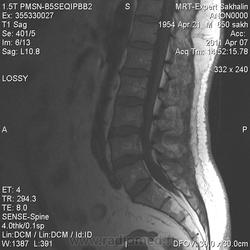

Учитывая, что сигнал подавился на FS, скорее да, жировая дегенерация. В случае гемагиомы с большим содержанием жировой стромы будет ли на FS подавлятся сигнал незнаю. Надо будет выяснить экспериментальным путем. :-)

Реконверсия -обратное замещение жирового костного мозга кроветворным при патологических состояниях, сопровождающихся повышением потребности организма в кроветворении.